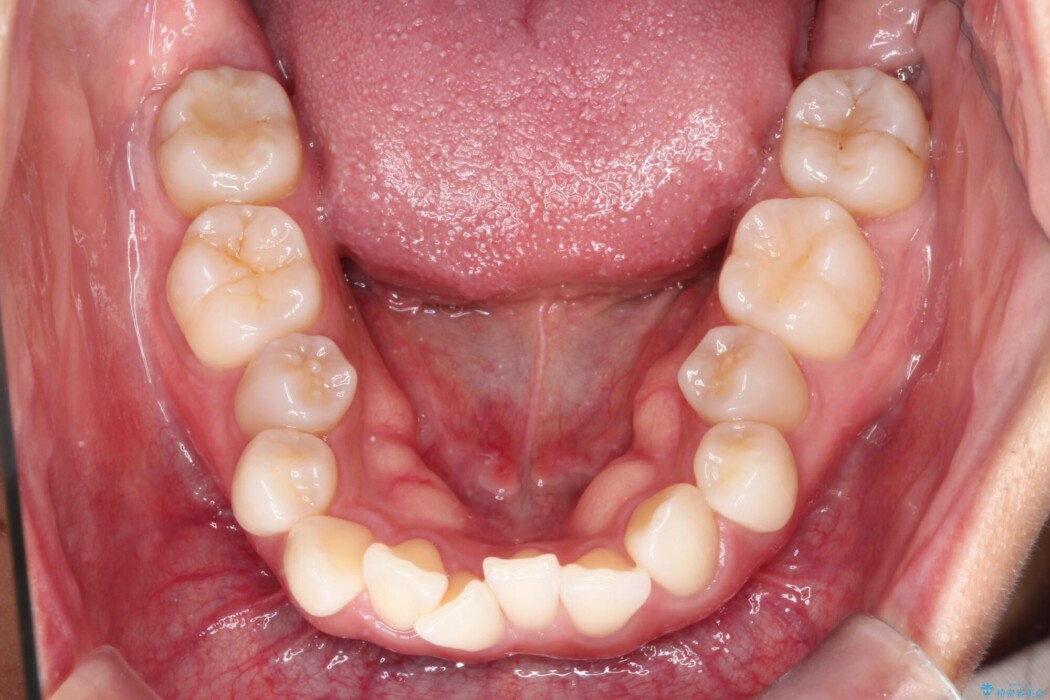

上下のガタつきと、右上の奥歯が外側に飛び出して上下が正しく噛み合わないシザーズバイトの改善のためにご来院された患者様です。

矯正検査の結果、右上7番が頬側に大きくズレており、うまくかみ合っていない状態でした。

まずはこの装置で奥歯の土台を安定させつつ、ワイヤー装置による繊細な歯の移動を組み合わせることで、非抜歯で歯列全体のアーチを整えていきました。シザーズバイトが解消されたことで、奥歯でしっかりと物を噛めるようになり、顎の動きもスムーズに改善されました。